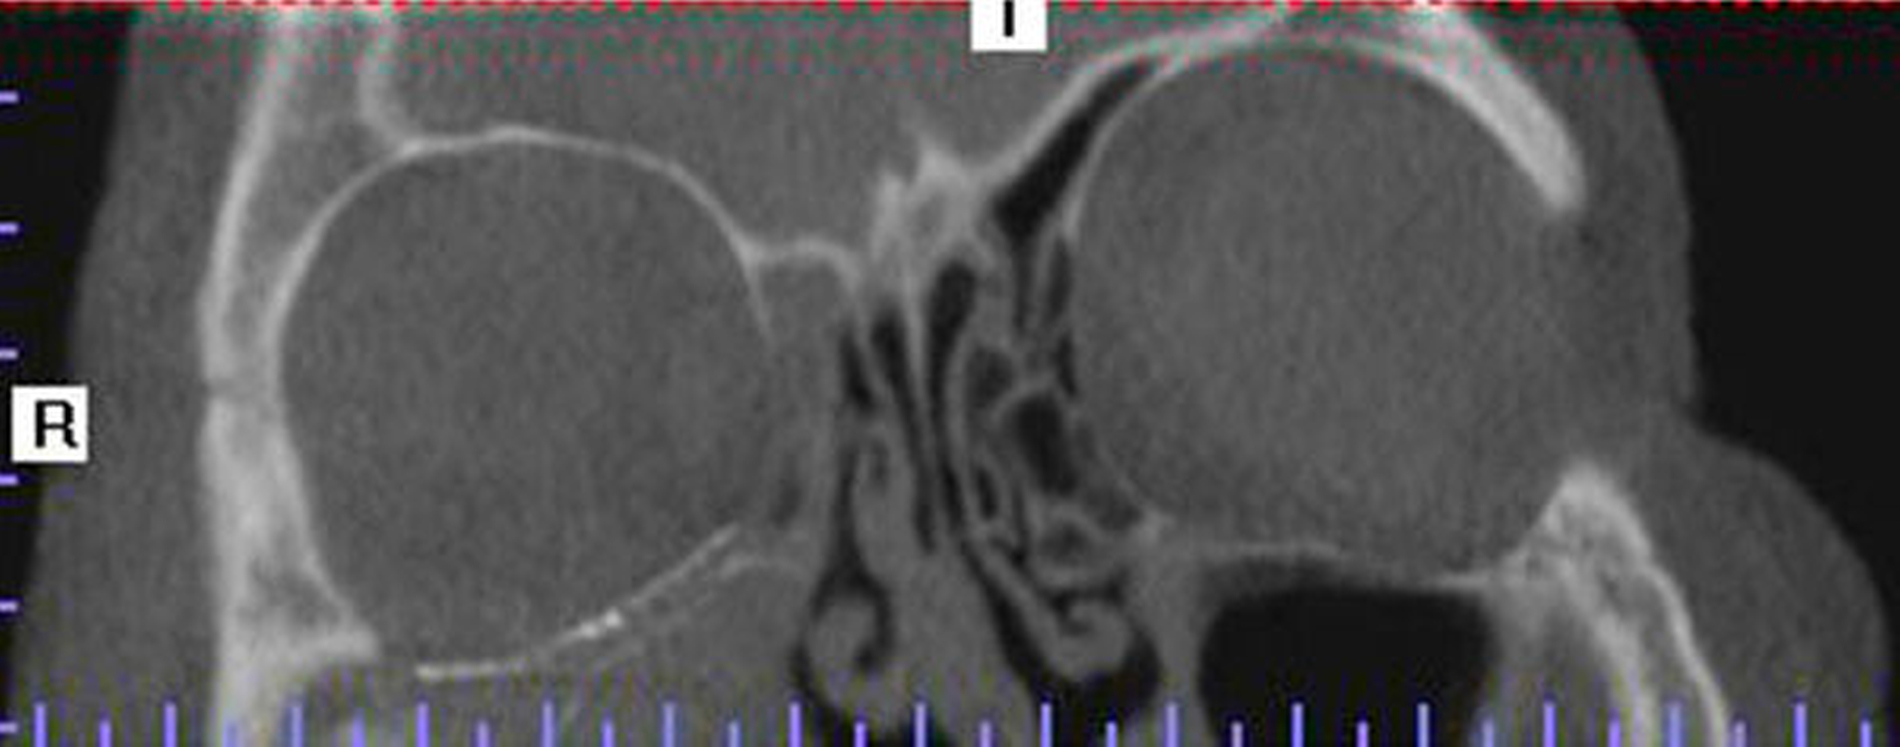

Im Rahmen der radiologischen Diagnostik wurden computertomografische Untersuchungen des Schädels, des Craniums und der Halswirbelregion durchgeführt. Hier zeigte sich der Kochtopfstiel 10 cm in situ steckend von oben kommend den rechten Orbitarand durchbrechend. Der Fremdkörper steckte mit dem Stiel voraus im rechten Mittelgesicht. Es zeigte sich nach intraoral keine Perforation.

Nach dem Notfalleingriff mit Weichgewebsversorgung der infraorbitalen Wunde wurde eine Orbita-CT zur Kontrolle und zum Ausschluss eines retrobulbären Hämatoms sowie einer Bulbusperforation durchgeführt. Der Bulbus stellte sich rund und normal dar, ohne Hinweise auf eine Perforation der Bulbuswand. Der Nervus opticus zeigte sich intakt. Es waren keine Anzeichen einer Herniation der Augenmuskulatur bei Orbitabodenfraktur zu sehen.